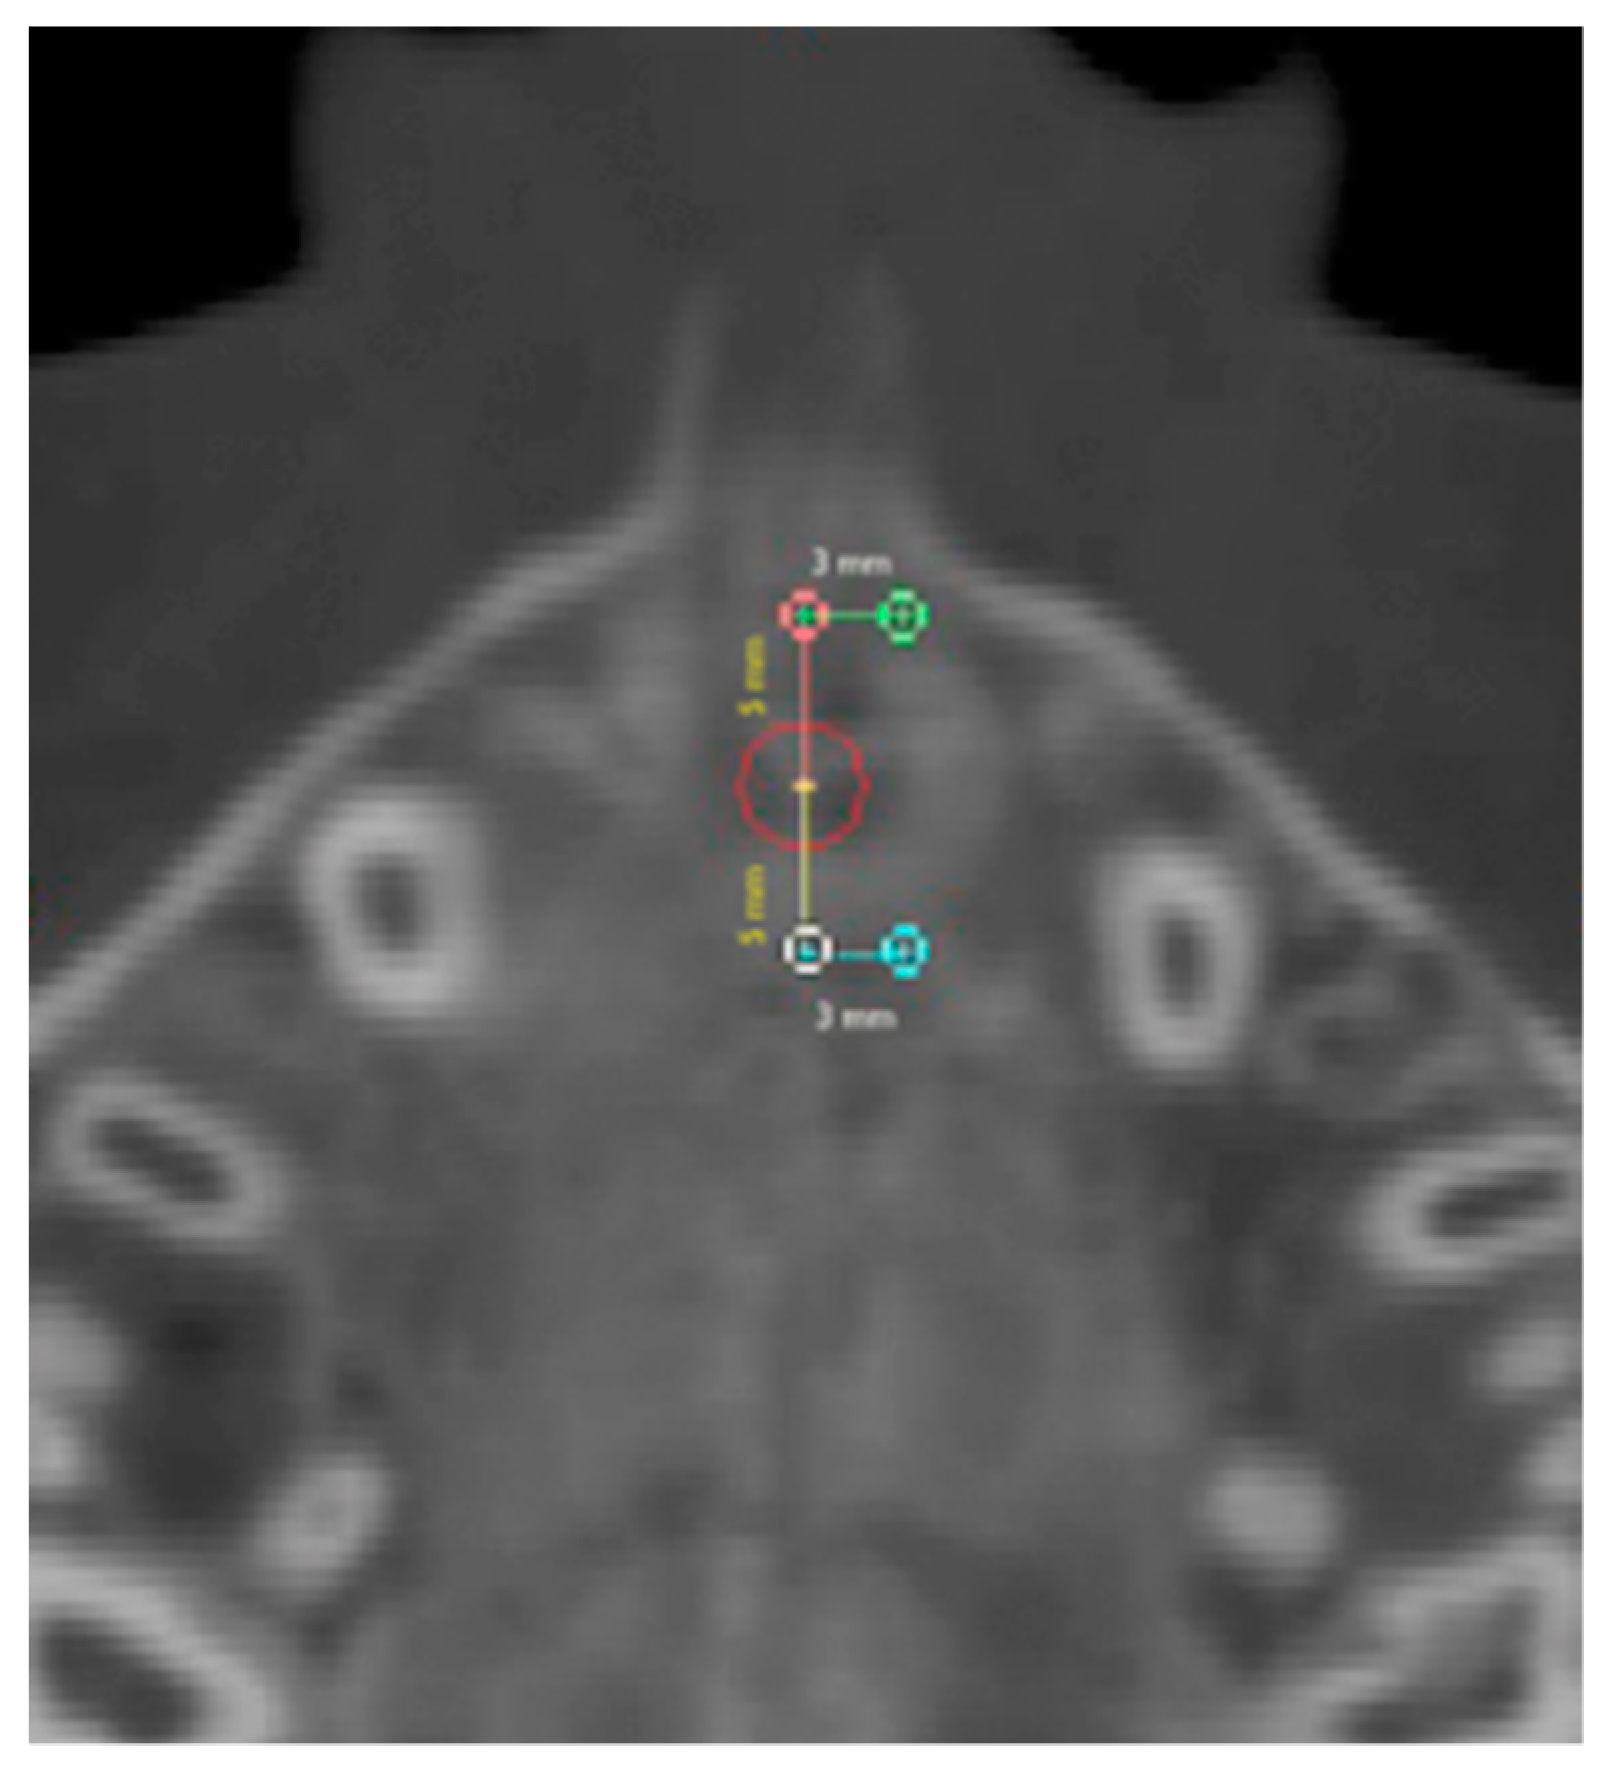

Six regions of interest (ROI) have been traced by one trained operator or the calculation of values of density in Hounsfield units (HU) using the software tools. Four round-shaped ROIs (Figure 3) and two rectangular-shaped ROIs (Figure 4) noted by previous studies [21,23] have been identified as follows.

2.2. Rectangular-Shaped ROIs

For the identification of the rectangular-shaped ROIs, a rectangular area was selected along the midpalatal suture starting from the landmark located 5 mm in front of the center of the nasopalatine duct and extending the entire length of the suture to the posterior nasal spine (PNS). The width of the rectangle was defined as 3 mm to the left and right side (total width 6 mm) of the center of the nasopalatine duct.

Anterior suture density (ASD) ROI: values of density measured in the ROI located along the midpalatal suture in a rectangular area starting from 5 mm in front of the center of the nasopalatine duct to the anterior half-length of the suture.

Posterior suture density (PSD) ROI: values of density measured in the ROI located along the midpalatal suture in a rectangular area extending from the posterior end of the ASD ROI to posterior half-length of the suture.

Figure 4. Rectangular-shaped ROIs.